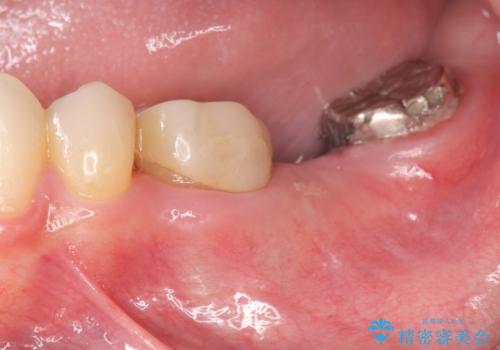

- 保険治療を繰り返し、口腔内全体の長期的な予後に不安があり全体的な治療を希望され来院されました。

左下には親知らずを支台とした設計に無理のあるブリッジが装着されており、根管治療も不十分な状態です。

設計に無理のある補綴(今回は親知らずを用いたブリッジ)は、プラークの堆積を起こしやすく虫歯や歯周病などのちに大きな問題を起こす原因となりえます。